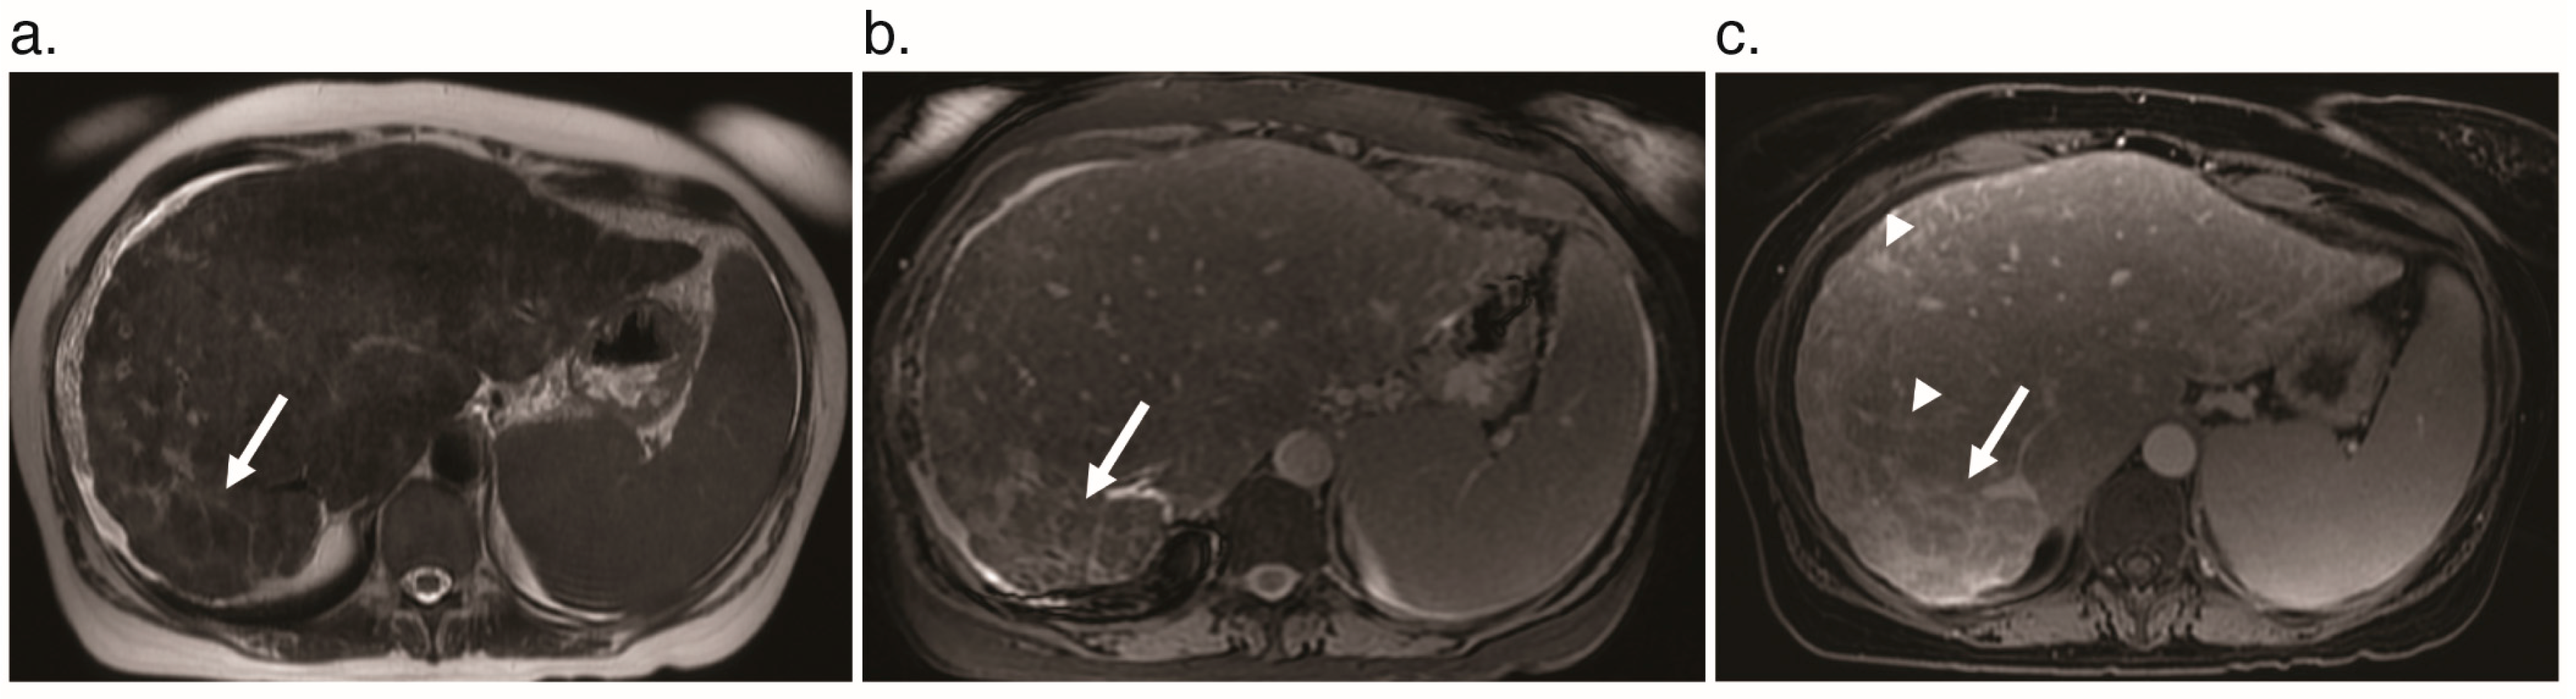

6.1. Pseudocirrhosis

- Cooney, T.; Sweeney, E.C.; Coll, R.; Greally, M. ‘Pseudocirrhosis’ in hereditary haemorrhagic telangiectasia. J. Clin. Pathol. 1977, 30, 1134–1141. [Google Scholar] [CrossRef] [PubMed]